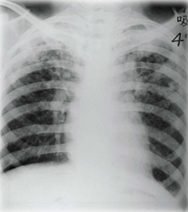

男,36歲。反復(fù)咳嗽,咳痰4年。多于上呼吸道感染后發(fā)生,膿性痰,有時(shí)痰中帶血,常伴發(fā)熱。期間3次胸部X線片檢查均為右下肺炎,經(jīng)抗感染治療可好轉(zhuǎn)。本次上感后再次出現(xiàn)咳嗽,少量膿性痰查體:右下肺可聞及中小水泡音。為明確診斷,宜首選的檢查

『正確答案』C

『答案解析』根據(jù)題干給出的條件,患者年輕男性,反復(fù)咳嗽咳痰,有咯血情況,抗感染治療有效,可以排除肺癌和肺結(jié)核,結(jié)合胸片,考慮此患者為支氣管擴(kuò)張,所以首選的檢查選擇C.